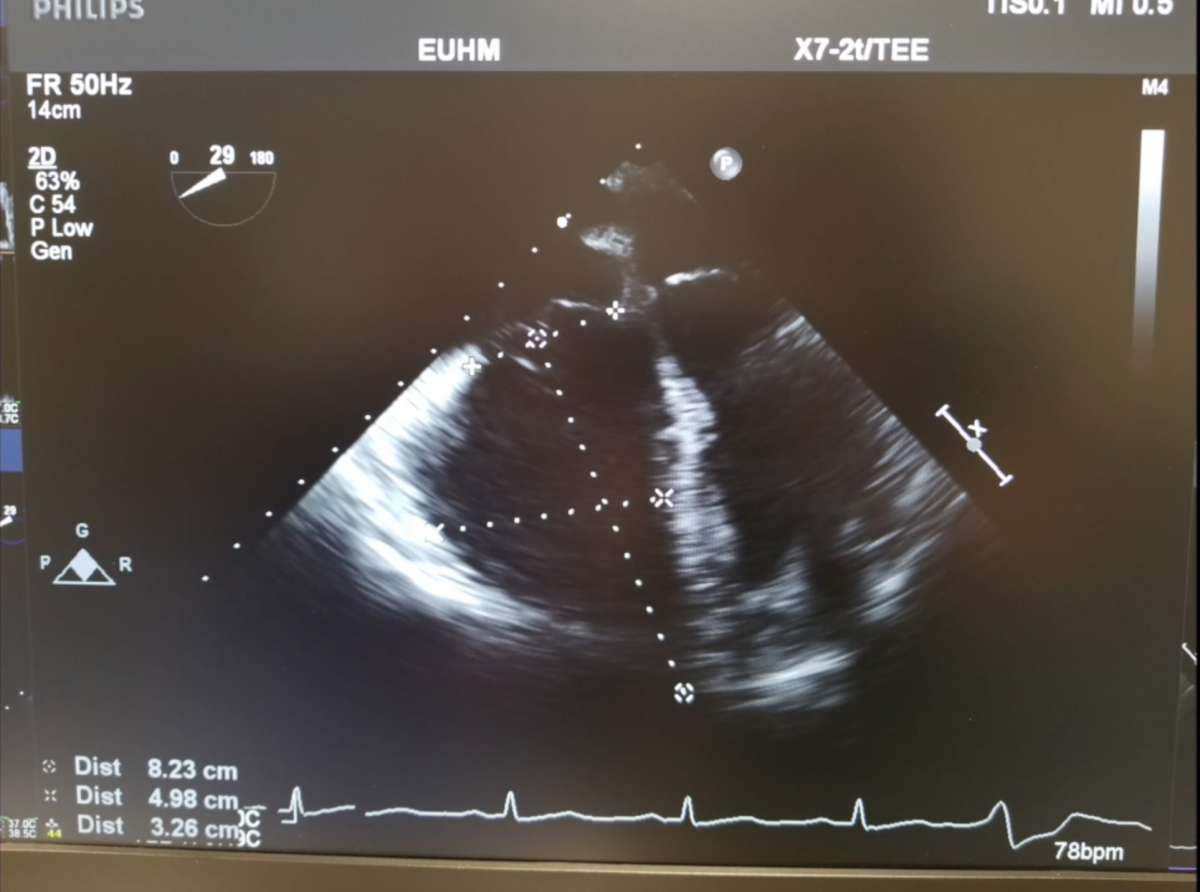

Surgical pulmonary embolectomy (SPE) is a safe and effective therapeutic approach to pulmonary embolism management for patients who are diagnosed with submassive and/or massive acute pulmonary emboli by clinical exam, supported by computed tomography (CT) and echocardiographic assessment. Other indications for surgical embolectomy include presence of thrombus-in-transit, concomitant cardiac pathology such as a large patent foramen ovale, or relative contraindications to thrombolytic therapy, including recent cerebrovascular or intracranial pathology, recent surgery, active bleeding, or other absolute contraindications to anticoagulation.

- Use the Seldinger technique to access the common femoral vein as follows: Access the vein with a needle and subsequent wire. Serially dilate the vessel to the size of the cannula. Insert venous cannula (25 French venous cannula) and position within the right atrium under TEE guidance. Connect venous line to bypass circuit.

- TEE availability